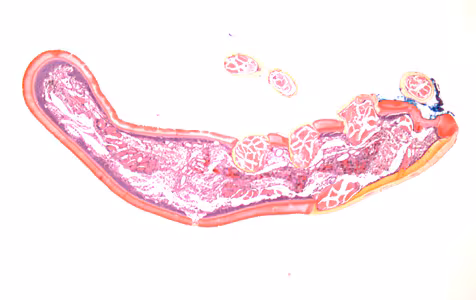

2015 DPDx Case Studies

DPDx Case Studies – 2015

DPDx is an educational resource designed for health professionals and laboratory scientists. For an overview including prevention, control, and treatment visit www.cdc.gov/parasites/.